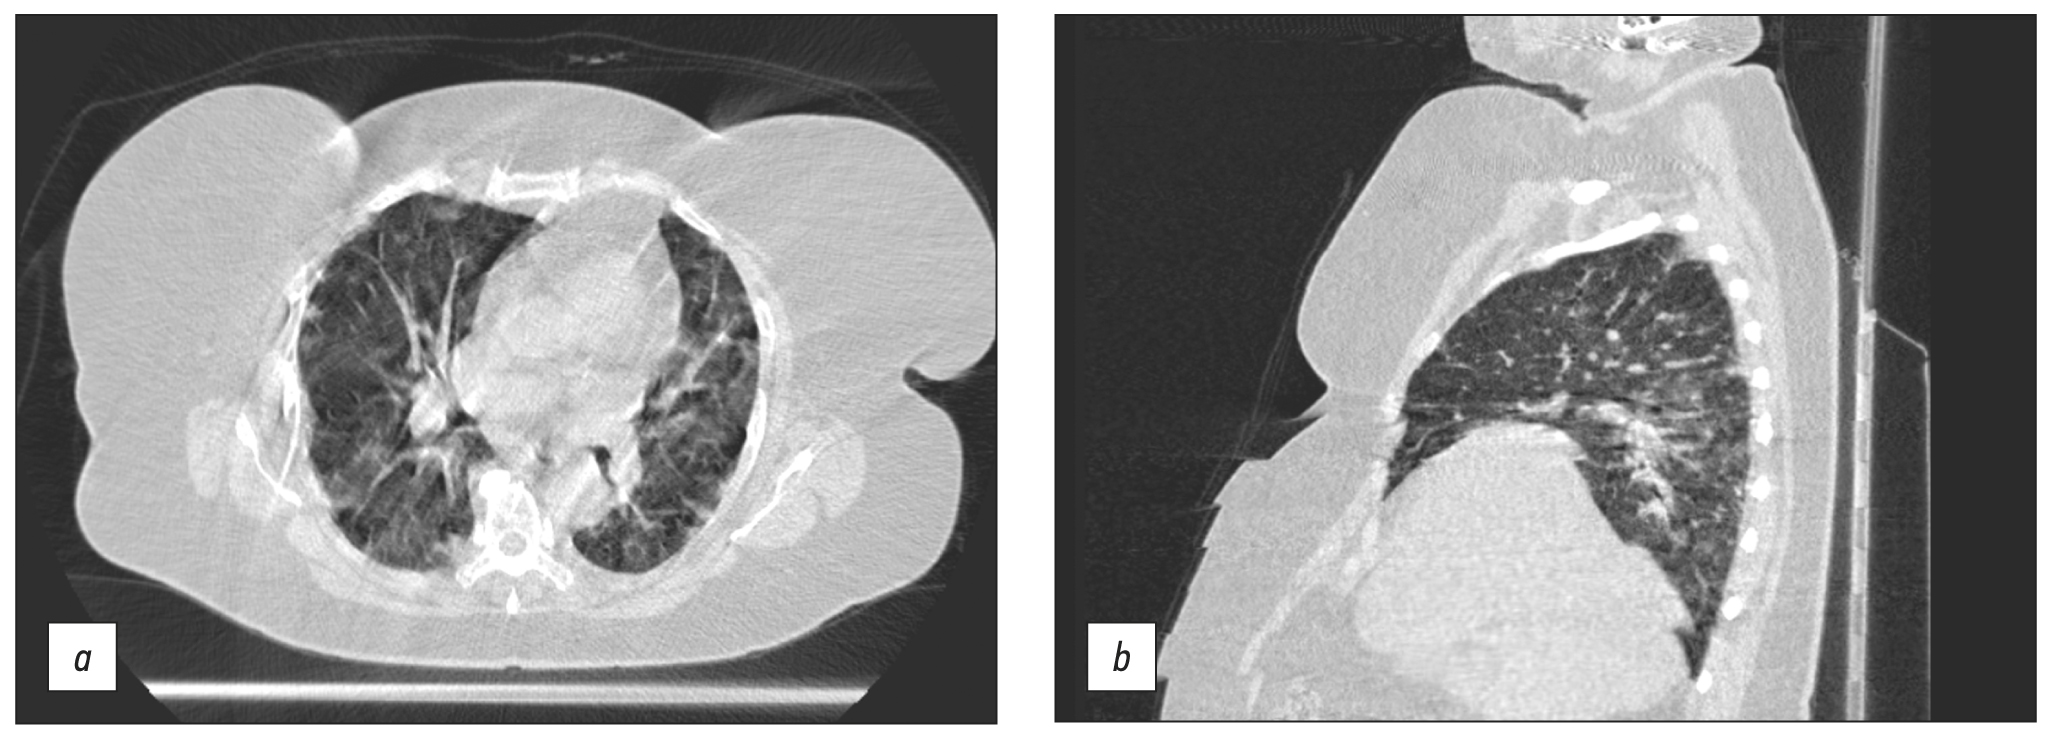

Long-term (15–25 s) scanning was too long for patients with respiratory insufficiency to remain their breath for the entire examination compared with stationary CT (3–5 s). As a result, motion artifacts (Fig. 6a) and steps (Fig. 6b) were present in CT images produced by breathing motions of the chest (Fig. 6).

Fig. 6. Axial and sagittal computed tomographic slices of chest organs in the lung window: (a) motion artifacts and (b) step artifacts caused by respiratory chest movements during scanning.

However, some limitations were observed, indicating that the present modification’s usage of a mobile CT was a forced solution. Some motion artifacts developed as a result of low scanning speed compared with stationary CT scanners. The caudal–cranial direction was proposed for chest CT scanning to limit the amount of respiratory artifacts [8]. Due to the configuration of the CT room (gantry movement was limited due to insufficient console wire length) in our situation of using Airo TruCT, such a solution proved unacceptable. The problem was fixed by postponing the command to hold the breath for 3–4 s after the scan began. Although the apical lung segment exhibited significant motion abnormalities and steps, the basal portions were clearly visible. This observation is significant because patches of ground-glass opacity or consolidation are precisely situated in the dorsal sections of the lower lobes in COVID-19 pneumonia [9]. Simple technical solutions, such as handheld transceivers and video communication, were also used to adopt off-label use of Airo TruCT. Due to the significant number of artifacts detected, additional scanning, reconstruction, and postprocessing algorithms should be developed, and scanning parameters should be optimized [10].